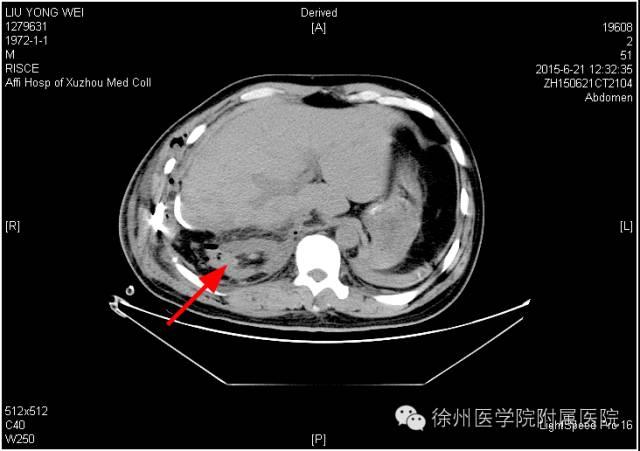

该声明称,患者手术时间是2015年6月20日,术后分别于2015年6月21日(术后第1天)和6月25日(术后第5天)的2次CT复查均显示该患者的右肾存在。

图一 2015年6月21日(术后第1天)CT,右肾如箭头所示。